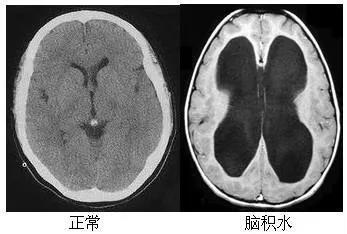

首先我们来个感性认识!上图看真相:

上图脑积水的影像图显示双侧侧脑室明显扩大(中间大大的黑蝴蝶)。如果我们看到这样的影像片子,一定要想到“脑积水”这个术语。

而,小帕的亲戚——正常压力脑积水(NPH),它有明显的脑积水影像学改变,但脑脊液压力并不高,仍然在 70~200 mmH2O(1 mmH2O = 0.0098 kPa)之间。